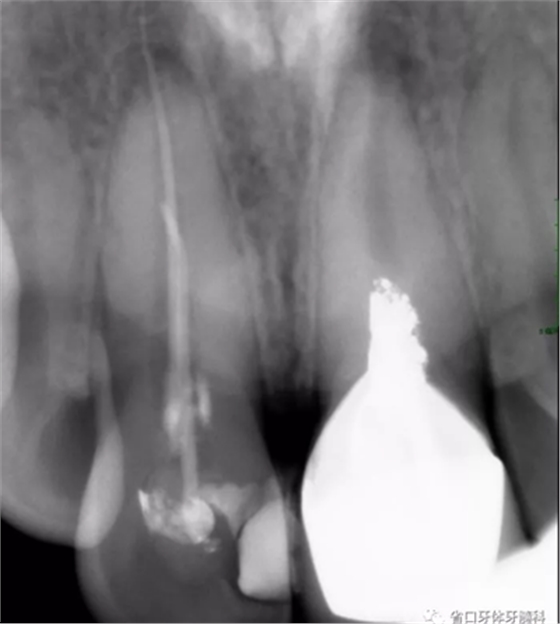

X線檢查:11冠部近中鄰面見高密度充填影像,邊緣有低密度線形暗影,根管內(nèi)見高密度稀疏影像,根管內(nèi)充填物與根管壁不密合,超出根尖孔約4-5mm,根尖周見低密度暗影;21根管上段修復(fù)體高密度影像,中下段根管空虛,根尖周見低密度暗影。圖3

圖3 治療前X線片